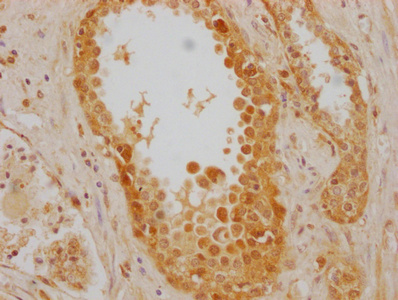

IHC image of CSB-MA010829A1m diluted at 1:220 and staining in paraffin-embedded human prostate cancer performed on a Leica BondTM system. After dewaxing and hydration, antigen retrieval was mediated by high pressure in a citrate buffer (pH 6.0). Section was blocked with 10% normal goat serum 30min at RT. Then primary antibody (1% BSA) was incubated at 4°C overnight. The primary is detected by a biotinylated secondary antibody and visualized using an HRP conjugated SP system.